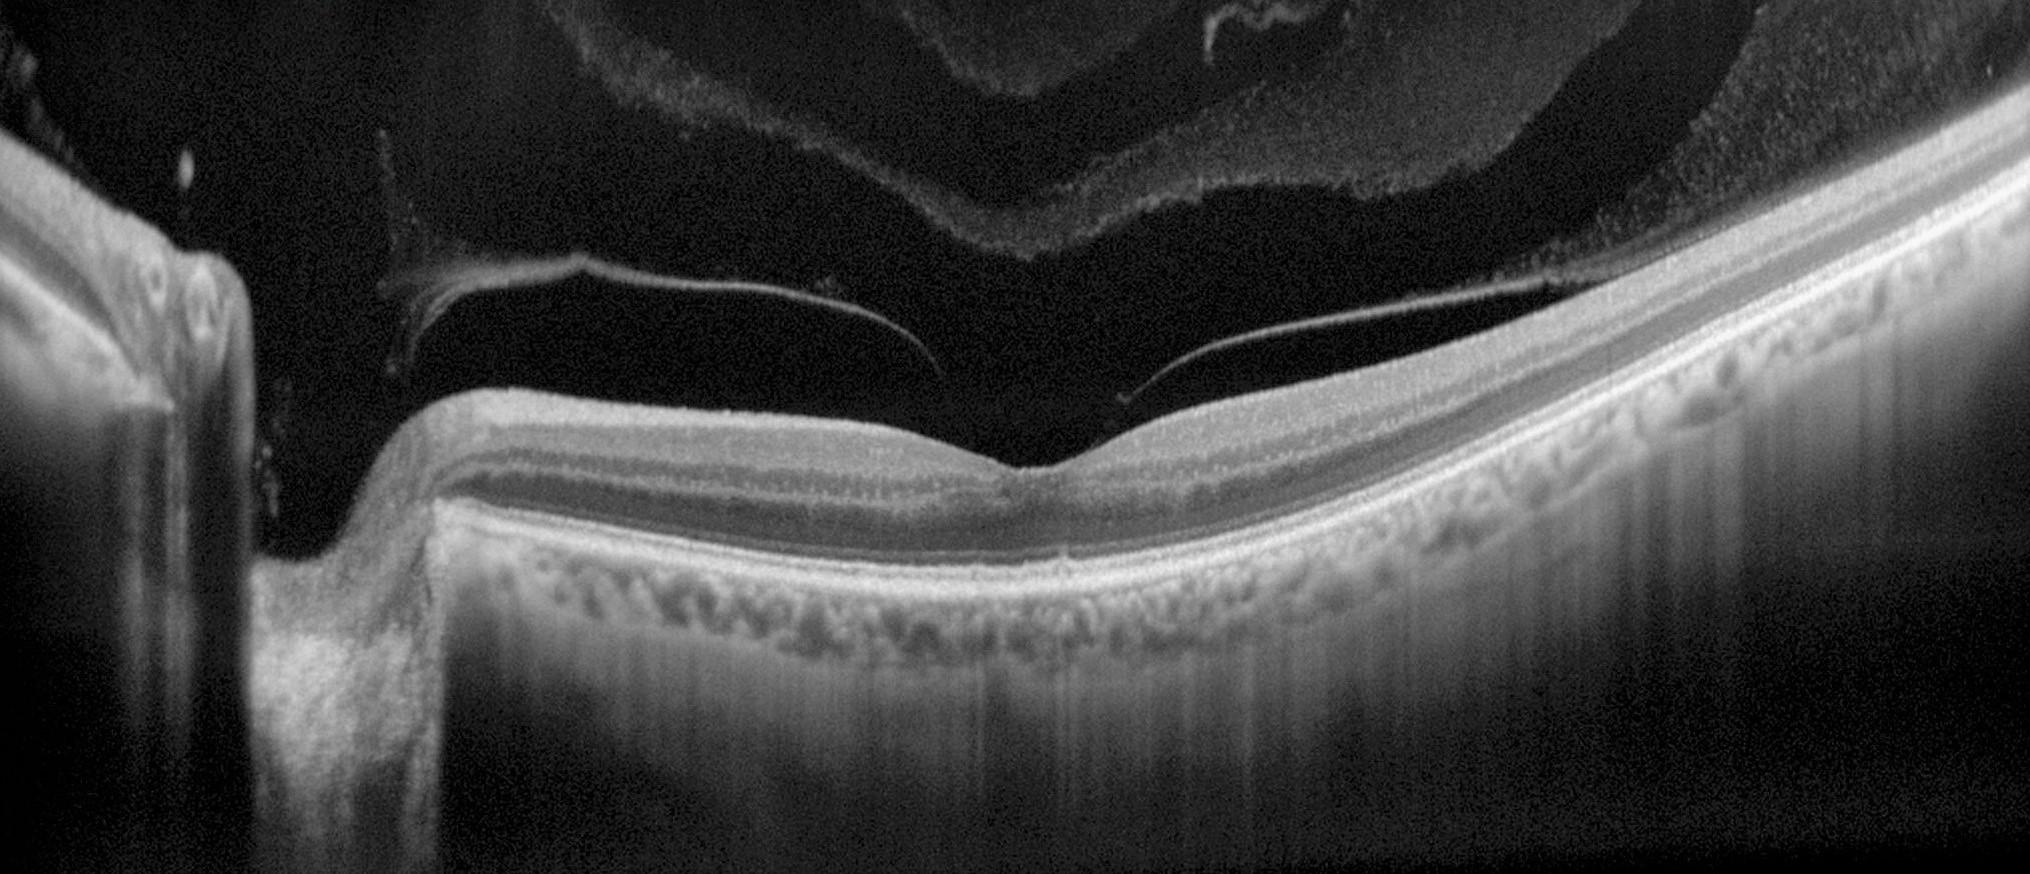

Pour une expertise plus poussée, d’autres modalités d’imagerie sont également possibles, plusieurs coupes OCT sont disponibles ainsi qu’une sommation des images jusqu’à 50 coupes (mode HD), un mode EDI pour la visualisation de la choroïde ou encore les modes photocouleur et OCT du segment antérieur.

Indications : Dispositif médical de Classe IIa / Certifié par le DEKRA Certification B.V. / CE0344. Le tomographe à cohérence optique RS-330 NIDEK avec la base de données normative est un système d’imagerie ophtalmique sans contact comportant un appareil photo numérique qui est adapté à l’observation et l’imagerie de visualisation par coupe axiale croisée des structures oculaires. Il est employé pour une imagerie et la mesure in vivo de la rétine, de la couche de fibre nerveuse rétinienne et de la papille optique comme moyen d’aide au diagnostic et à la gestion de la maladie rétinienne. En outre, l’adaptateur de segment antérieur de l’oeil (unité à lentille spéciale) montée sur la lentille d’objectif de l’appareil principal du système permet une observation de type non invasif et sans contact de la forme du segment antérieur de l’oeil tel que la cornée ou de l’angle de la chambre antérieure.